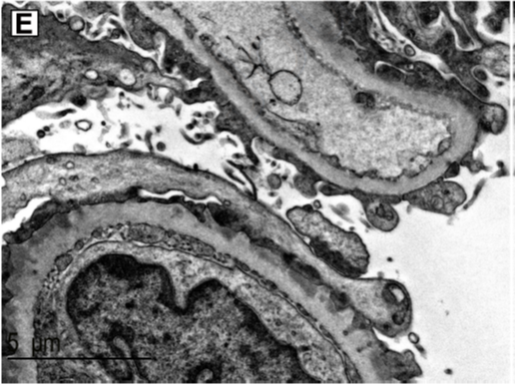

Here’s electron microscopy showing a capillary loop spared of deposits, adjacent to one with deposits, demonstrating this segmental nature of immune deposition. 9/21

This pattern is not seen in other types of membranous, including PLA2R, THSD7A, or EXT1/2 associated MN. 10/21